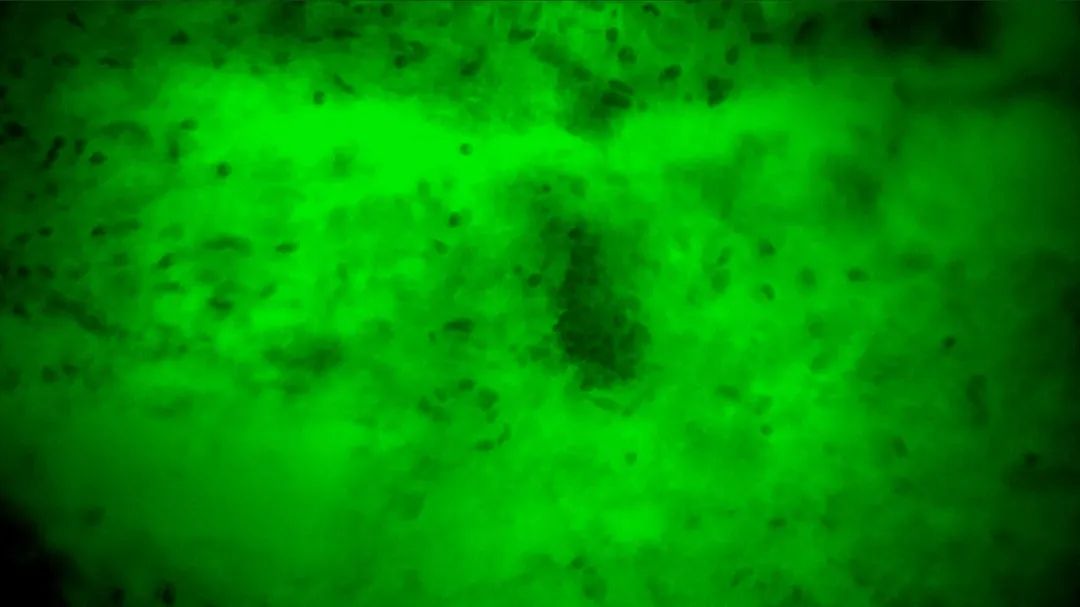

2

陽(yáng)性,細(xì)胞核異型、密集、分布不均勻